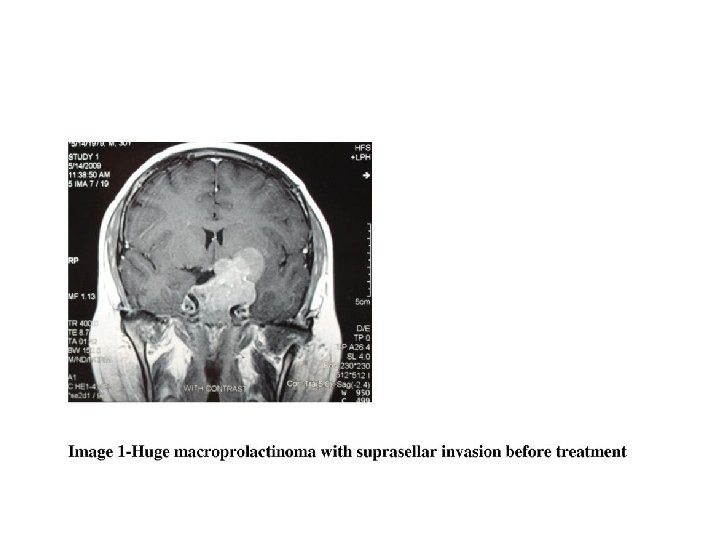

Macroadenoma management • Medical therapy regardless of size • Reassess vision within one month if initially abnormal (improvement may be observed within a few days) • Adenoma size decrease within weeks or months and can continue for years

Treatment • Medical: Dopamine agonists • Bromocriptine: initial dose, 1. 25 mg nightly, increased to 2. 5 mg bid in 1 -2 weeks, Doses larger than 7. 5 mg/d are seldom needed but in macroprolactinoma Microprolactinoma: 85%-90%: Nl. PRL in within days to a few weeks, Regular menses: a few months Macroprolactinoma: visual field improvement within 1 -3 days and reduction in tumor size as soon as 2 weeks • Cabergolin: more effective than bromocriptine Surgical: trans-sphenoidal